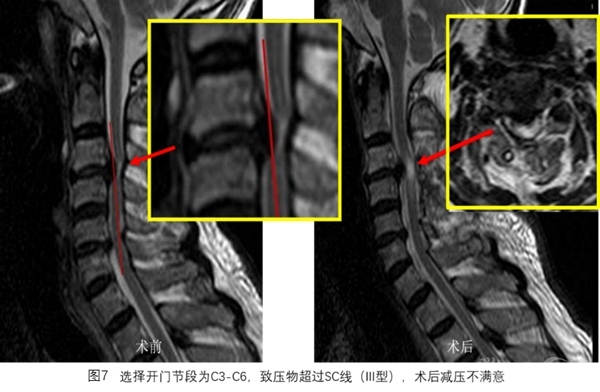

SC线同时反映颈椎管曲度、脊髓曲度与致压物的关系,根据SC线及其分型能更好地预测颈椎开门椎管成形术后脊髓减压的效果(图3~图8)。

在MR T2像脊髓矢状位上画线,具体方法见图1。根据SC线与前方致压物关系可分为3型:I型为致压物在SC线前方,II型为致压物与SC接触,III型为致压物超过SC线(图2)。

选择开门节段后,划出SC线,分型为I型开门术后减压满意,II型大部分可获得减压,III型减压不满意。